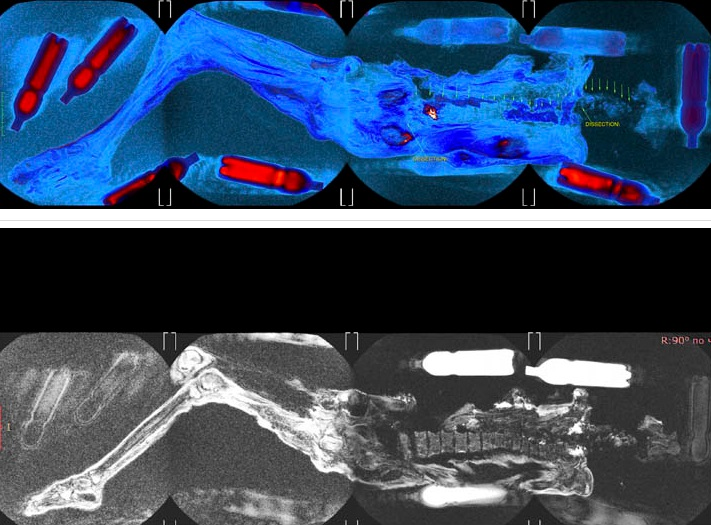

Kết quả chụp MRI cho thấy cô mắc ung thư vú giai đoạn cuối và viêm tủy xương, có thể là nguyên nhân chính dẫn đến cái chết khi mới 20-30 tuổi.(Ảnh: Dân việt)